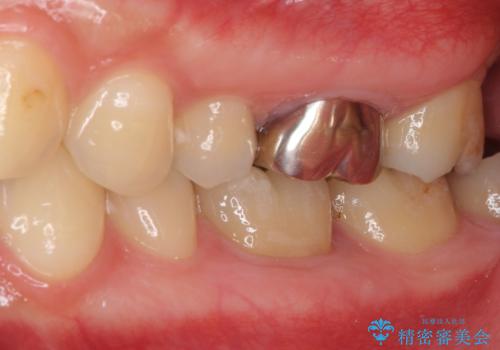

- 奥歯の虫歯と銀歯を気にして来院された患者様です。

セラミックインレーおよびセラミッククラウンによる治療を希望されましたが、虫歯となっている歯は神経近くにまで蝕まれていたため、長期的な予後を鑑みて、PGAインレー(プラチナゴールドインレー)にて修復することとしました。

ゴールドインレーを装着するまでは、金属色が目立ってしまうのではないかと心配されていましたが、表からは見えない位置にあること、銀歯と異なり目立つ色ではないことから、審美的な問題はありませんでした。